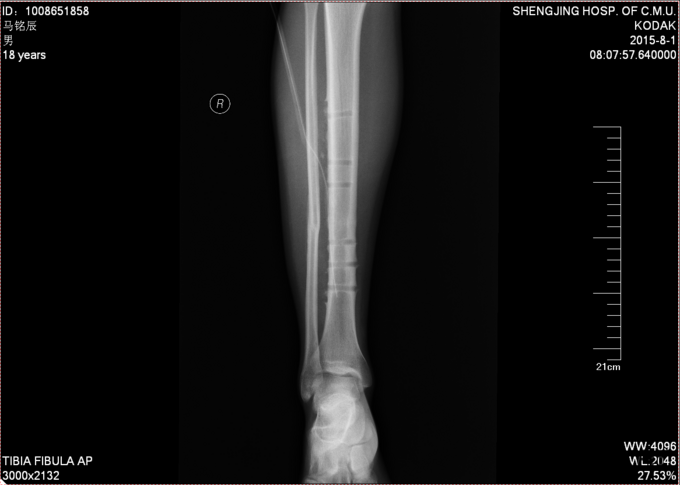

现病史:患者及家属自诉于2013年11月9日下午2点因打篮球摔伤致右小腿疼痛、肿胀,后于2013年11月11号于我院行胫腓骨骨折切开复位内固定术,现内固定物固定已一年半来我科继续治疗。病来无发烧发热,无咳嗽,无其他不良主诉,饮食二便正常,体重近期无明显变化。

患者入病房,右小腿处可见一约10cm瘢痕,瘢痕部无明显压痛,右下肢无轴向叩击痛,无明显肿胀,足趾背伸跖屈肌力5级,足背部及小腿感觉正常,双下肢等长。足背动脉可触及搏动。其余肢体未见异

入院后完善检查,及功能检查后,于全麻下行右胫腓骨骨折术后内固定物出去术,术后第二天换药示切口无红肿渗出,患者自动退院。